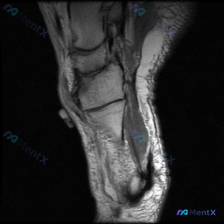

这是一份足踝部矢状位T2加权MRI图像,覆盖后足区域(跟骨、距骨、距下关节、跟腱附着区),具体影像发现如下:

- 骨骼信号:跟骨后部及体部可见广泛弥漫混杂T2高信号,提示骨髓水肿/充血/炎症;距骨体后部也可见边界模糊的信号改变,同样提示骨髓水肿

- 肌腱软组织:跟腱近止点处信号明显增高、增厚(正常跟腱T2为均匀低信号),提示跟腱病变/止点炎症;跟骨后方周围软组织可见片状高信号,提示炎性水肿/跟骨后滑囊炎

- 关节情况:距下关节可见少量积液